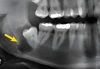

# 18. Retention of the teeth. Etiology, pathogenesis, clinical features Etiology of tooth retention

* **Rickets** * **Devitalized deciduous teeth=>** delay root resorption preventing normal eruption of permanent teeth * **Dystopia** (incorrect positioning) or **partial anodontia** (lack of a germ of the respective permanent tooth)=> * Deciduous tooth remains in the alveolar process longer than usual. * **Genetic factors**

133

# 18. Retention of the teeth. Etiology, pathogenesis, clinical features Differential diagnoses for tooth retention

* **Delayed eruption** due to nutritional deficiencies or systemic conditions like rickets. * Presence of **supernumerary teeth** which might prevent the eruption of permanent teeth

134

# 18. Retention of the teeth. Etiology, pathogenesis, clinical features Treatment options for retained teeth

* **Operative** **Treatment**: **Extraction** if the retained tooth causes complications=> * such as **cysts** or **infections**. * **Surgical**-**Orthodontic** **Treatment**: (e.g., canines), * Bone above the tooth is removed and the tooth is gradually moved to proper position

135

# 18. Retention of the teeth. Etiology, pathogenesis, clinical features Complications that can arise from retained teeth

* **Infections** and **cyst formation** around the retained tooth. * Formation of **dental abscesses.** * **Displacement or crowding** of adjacent teeth. * **Resorption of roots** of adjacent teeth. * Potential impact on development of the **dental arch and occlusion problems**